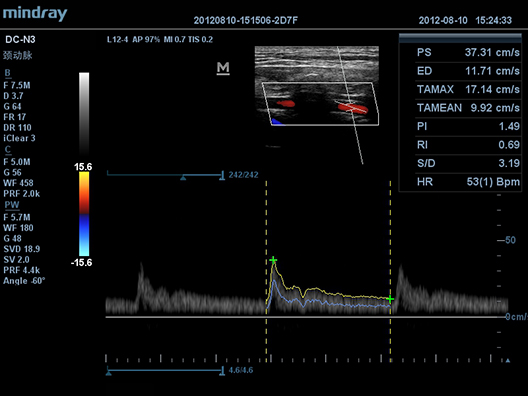

DC-N3

–£–ó-—Å–∫–∞–Ω–µ—Ä DC-N3 –ø—Ä–µ–¥—Å—Ç–∞–≤–ª—è–µ—Ç —Å–æ–±–æ–π –æ–ø—Ç–∏–º–∞–ª—å–Ω–æ–µ —Å–æ—á–µ—Ç–∞–Ω–∏–µ –∫–∞—á–µ—Å—Ç–≤–∞, —É–Ω–∏–≤–µ—Ä—Å–∞–ª—å–Ω–æ—Å—Ç–∏ –∏ –¥–æ—Å—Ç—É–ø–Ω–æ—Å—Ç–∏ –∏ —è–≤–ª—è–µ—Ç—Å—è –Ω–∞—Å—Ç–æ—è—â–∏–º –ø–µ—Ä–µ–æ–ø—Ä–µ–¥–µ–ª–µ–Ω–∏–µ–º –æ—Å–Ω–æ–≤, –æ–±–µ—Å–ø–µ—á–∏–≤–∞—è –ª—É—á—à—É—é –≤ —Å–≤–æ–µ–º –∫–ª–∞—Å—Å–µ —Ñ—É–Ω–∫—Ü–∏–æ–Ω–∞–ª—å–Ω–æ—Å—Ç—å –∏ —ç—Ñ—Ñ–µ–∫—Ç–∏–≤–Ω–æ—Å—Ç—å –ø–æ —Ä–∞–∑—É–º–Ω–æ–π —Ü–µ–Ω–µ.